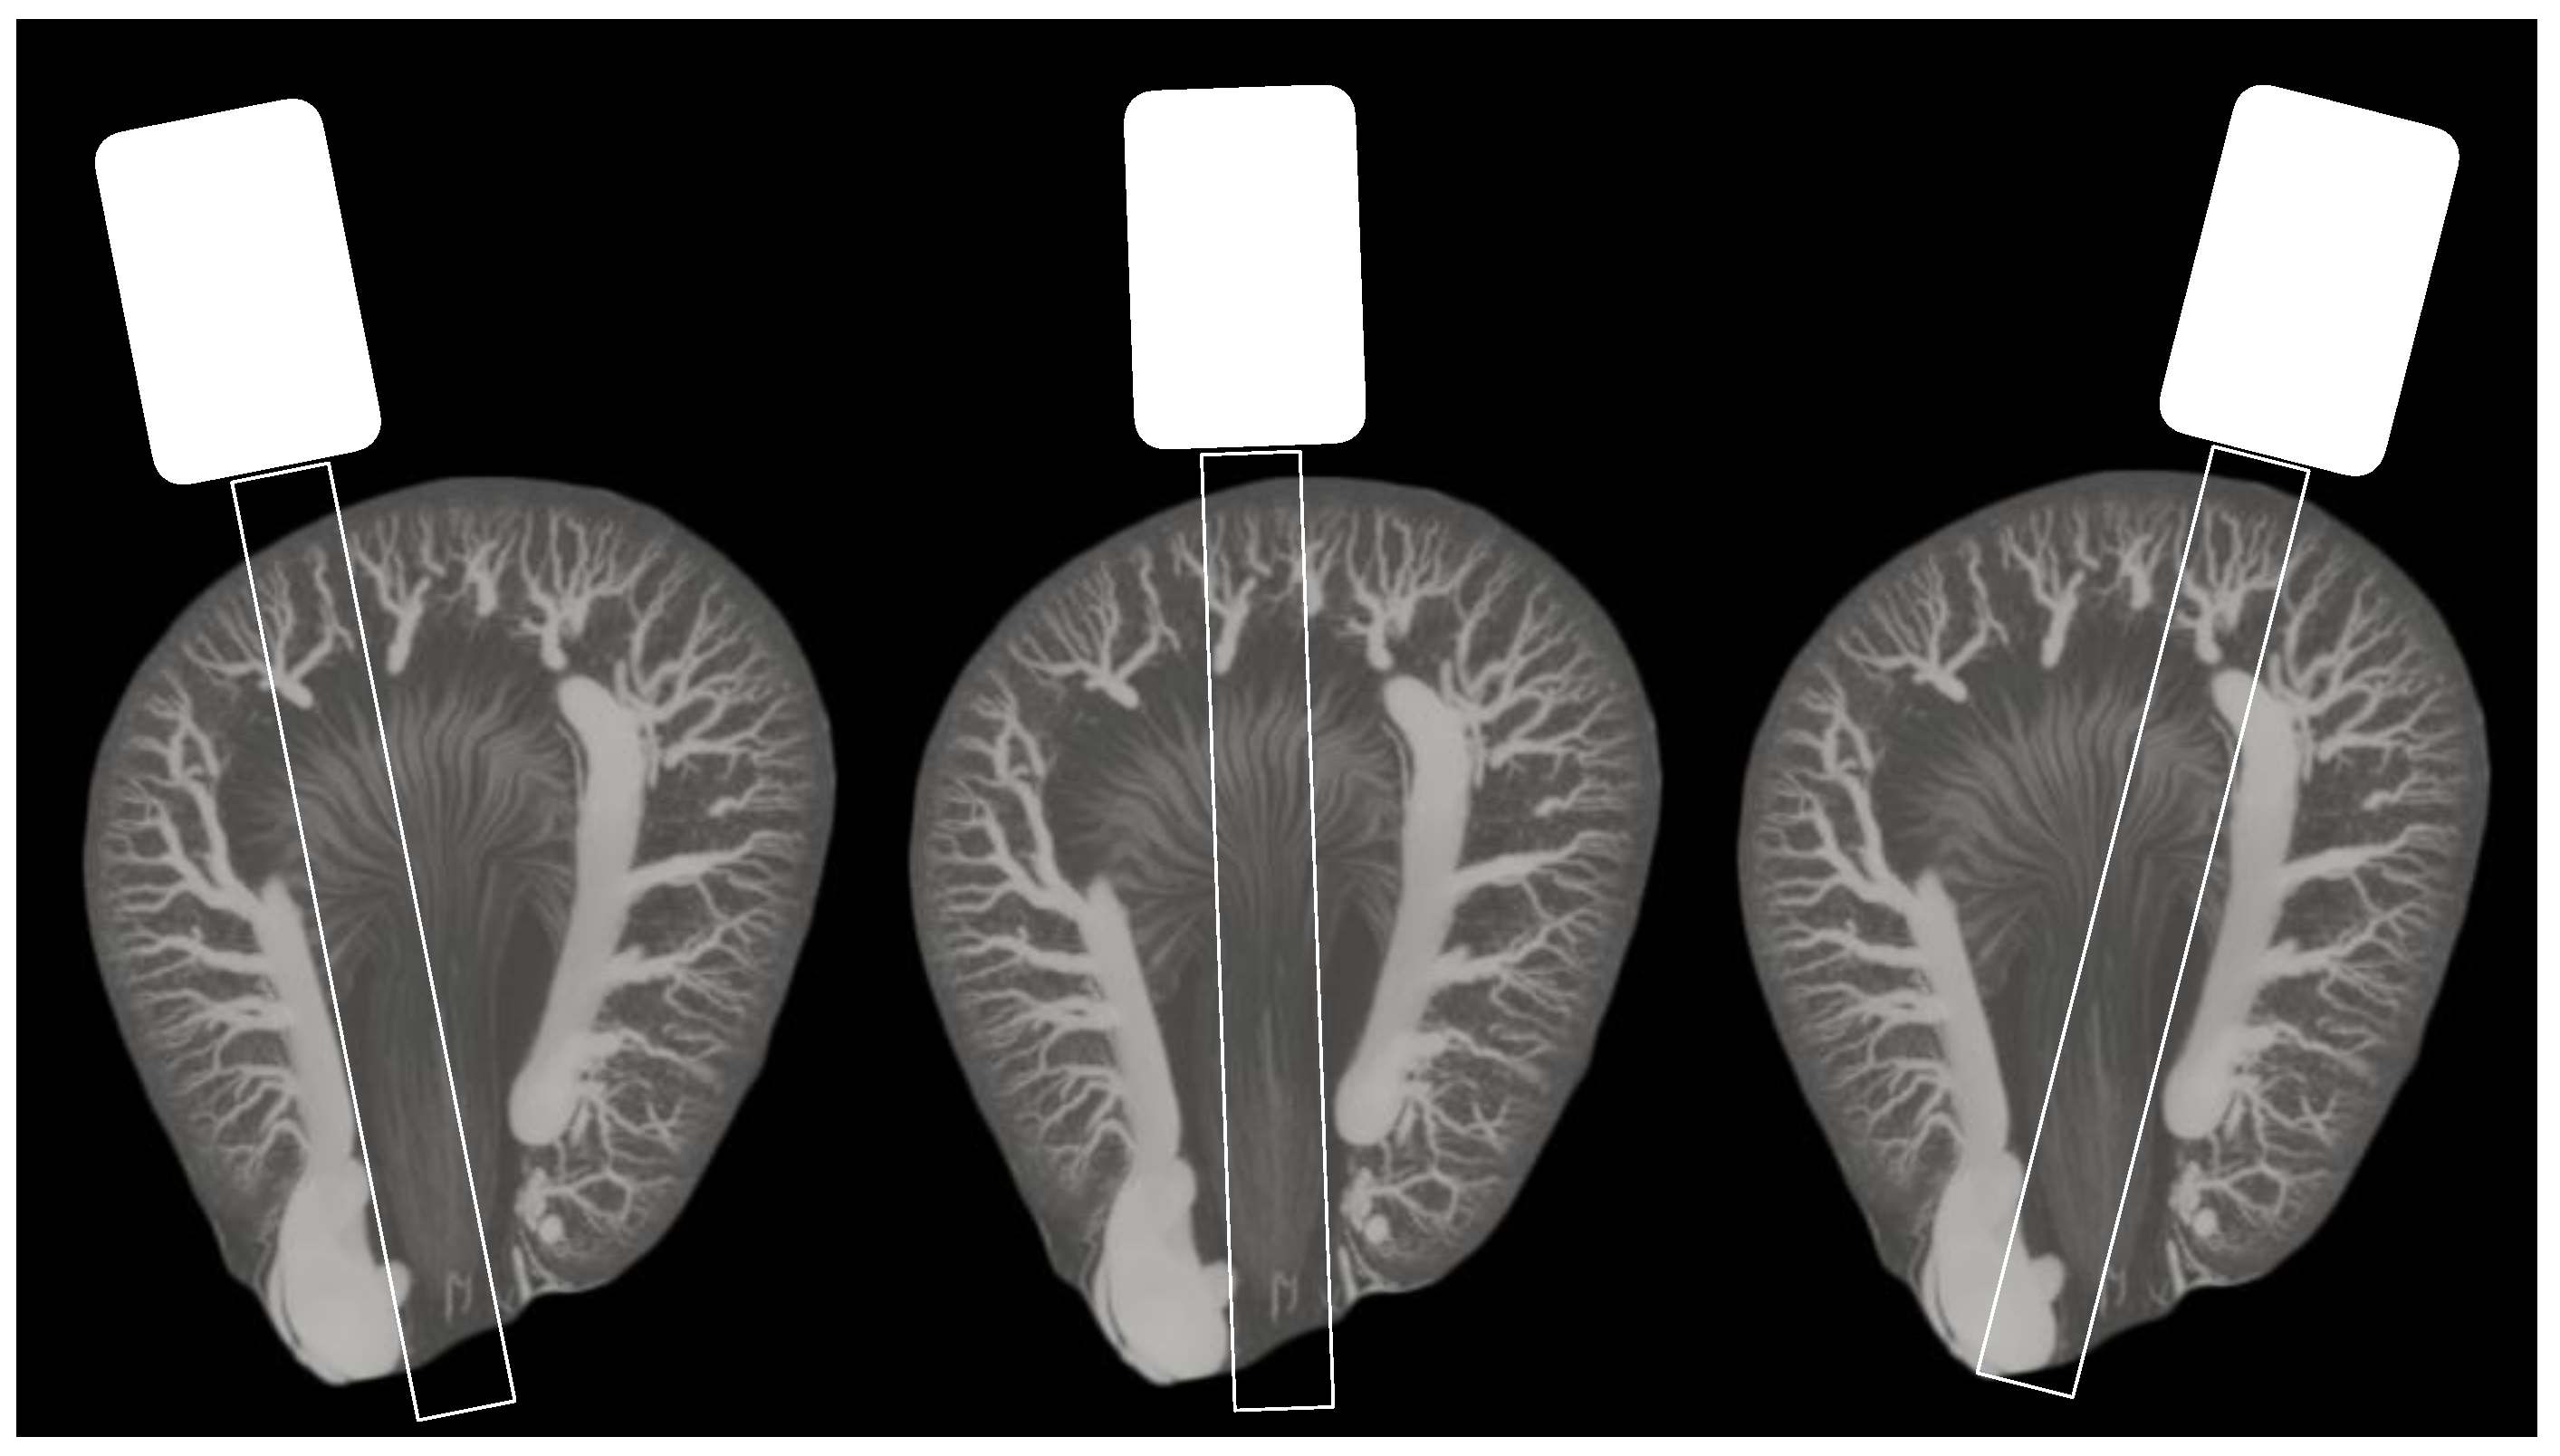

2. Materials and Methods